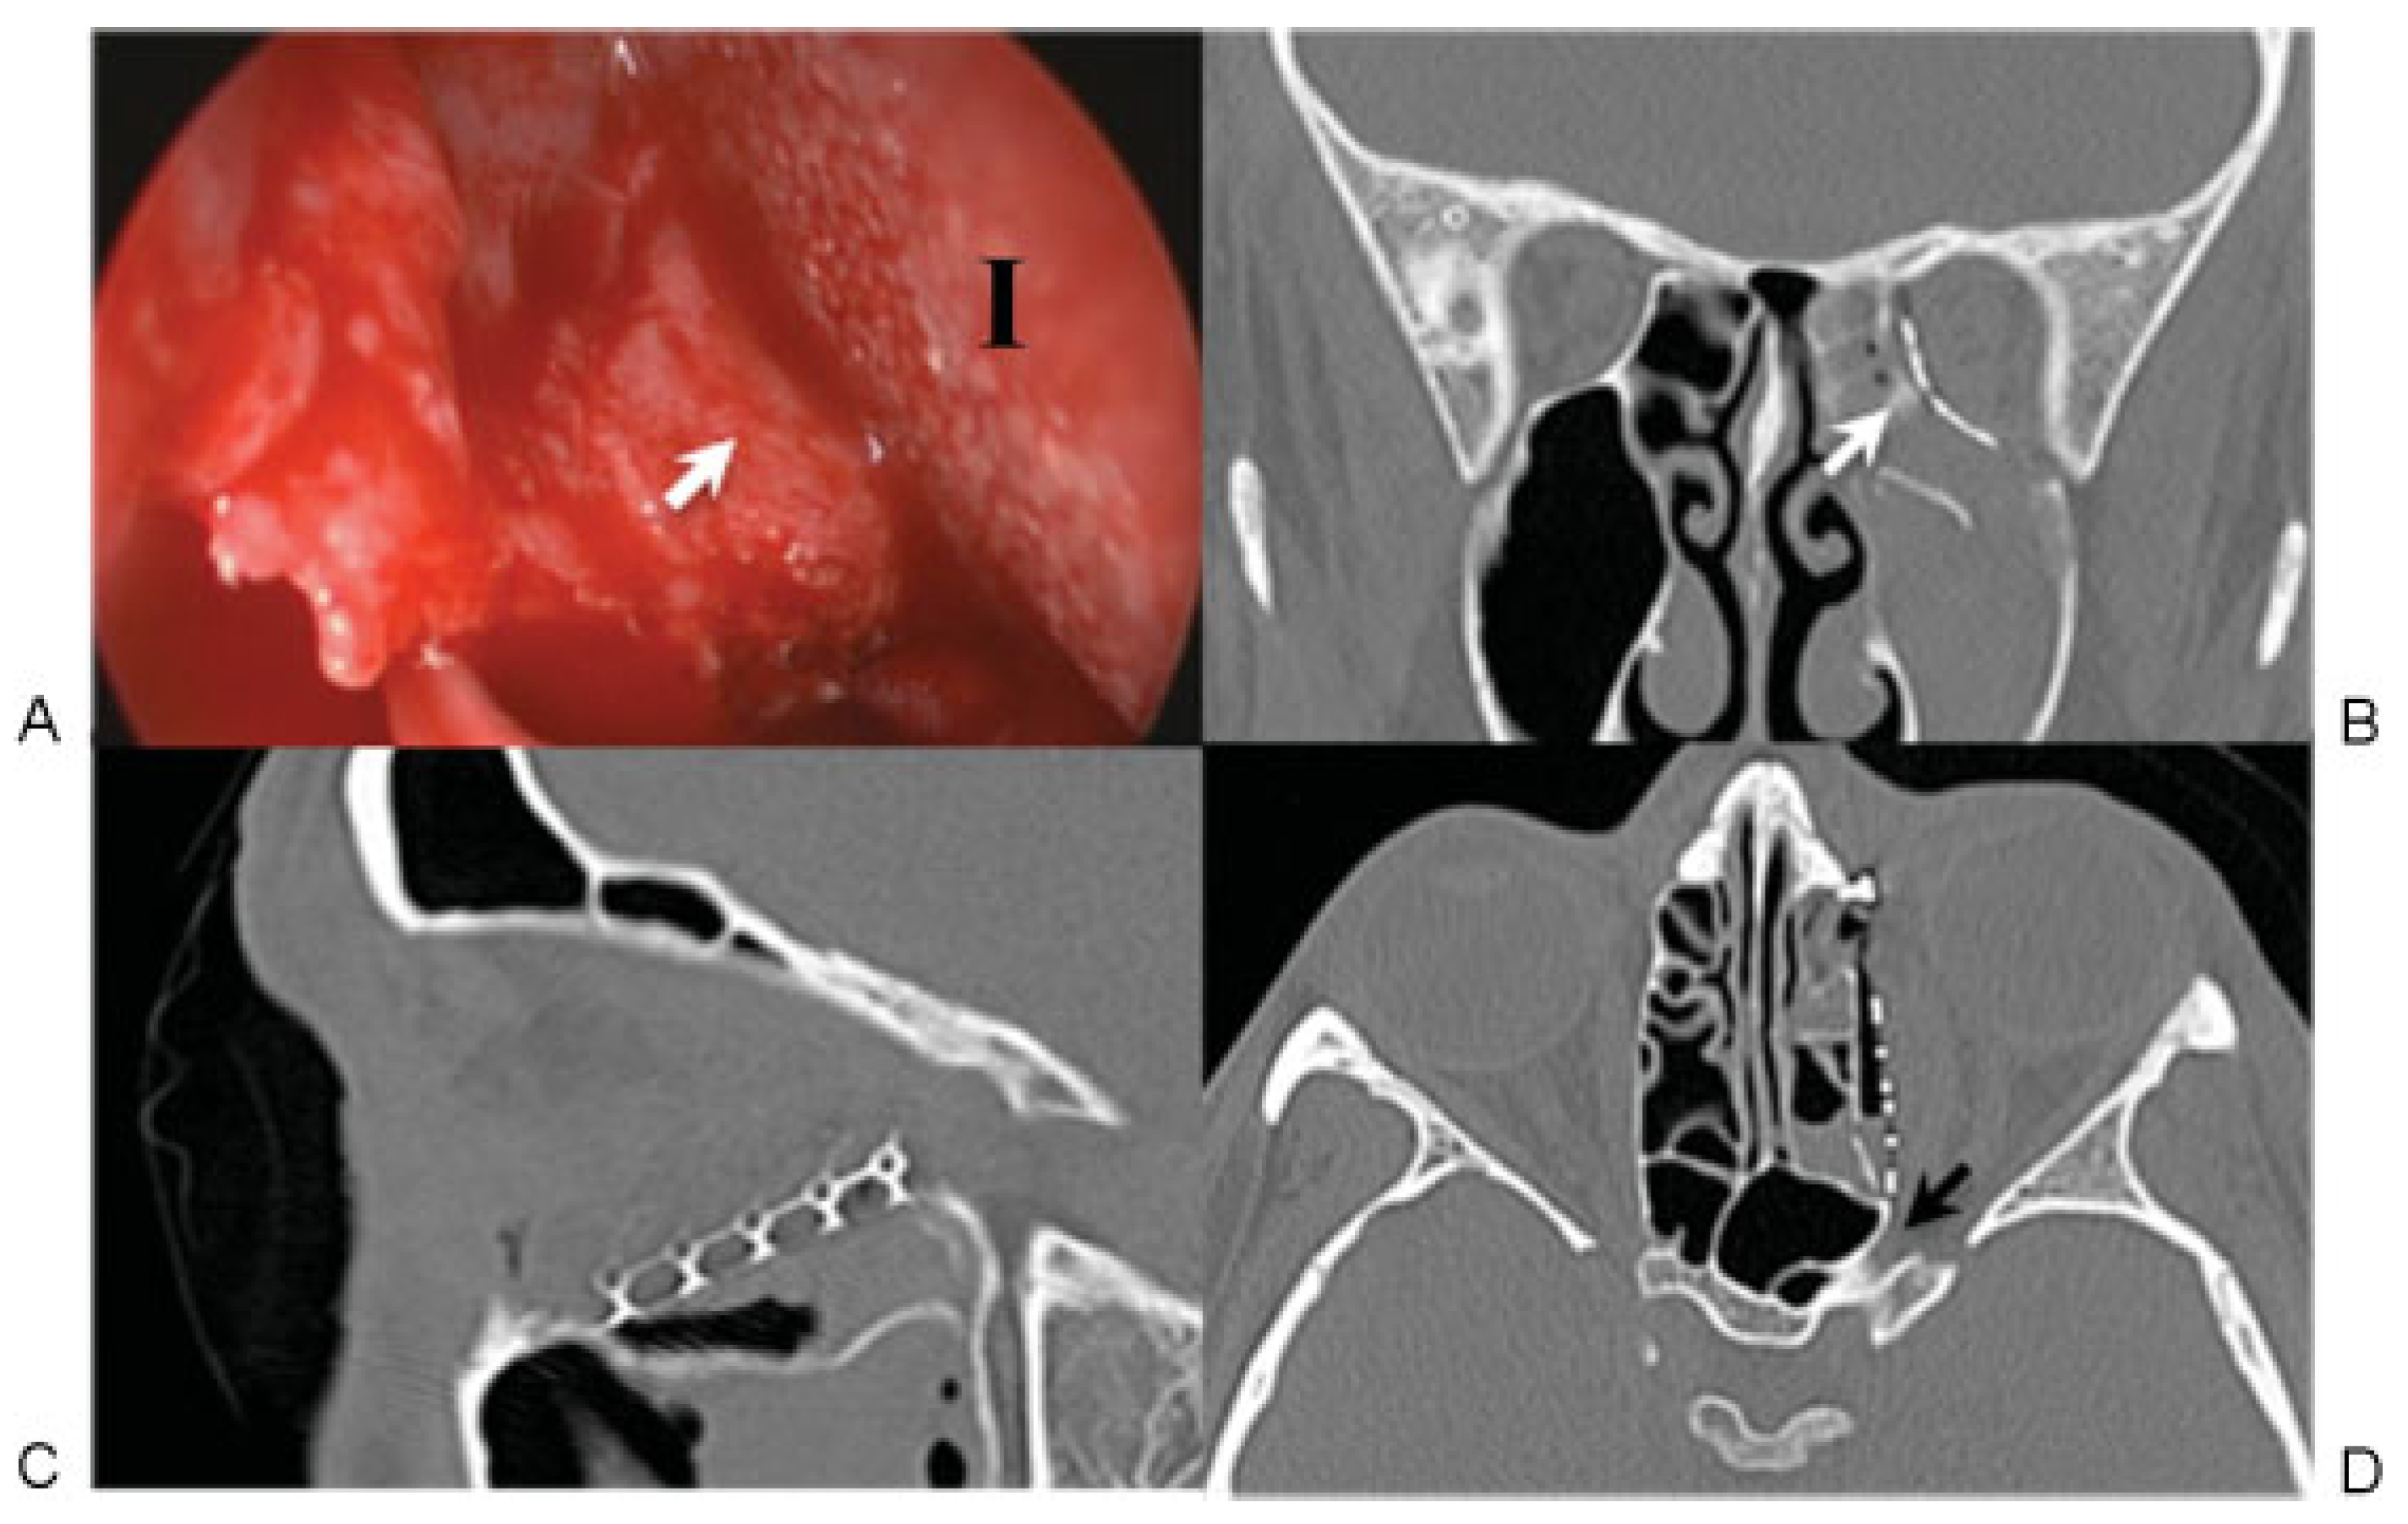

Positioning of the implant on stable ledges of bone is also critical, as no implant, no matter how well designed or shaped, will serve its purpose if not placed anatomically. Anterior and lateral bony ledges are relatively easy to obtain, but the most important and most problematic support points are the posterior and superior ledges. Failure to support the implant on these ledges was implicated in all eight of the cases referred to us for revision (Figure 5 and Figure 6), as well as two of the three author’s cases needing revision. Posterior floor and medial wall support are critical but often lacking, and many surgeons are loath to venture so far into the orbit for fear of injuring the optic nerve. However, meticulous plan-ning, a solid knowledge of orbital anatomy, and the use of adjunctive surgical techniques can decrease this risk. Intra-operative measurements of orbital depth can be compared with preoperative CT scan measurements, and the posterior ethmoidal foramen can serve as a vital anatomic reference point relative to the optic nerve. Other potentially useful modalities include intraoperative CT scanning, surgical navi-gation devices, and sinus endoscopy (Figure 7). The superior ledge is also critical to proper implant placement and is usually found at the level of the frontoethmoid suture. An excellent way to verify the location of this landmark is to divide the anterior and posterior ethmoidal neurovascular bundles and continue dissecting subperiosteally to the medi-al orbital roof. Care must be taken not to mistake the fovea ethmoidalis for the orbital roof, particularly when the medial wall is displaced far into the ethmoid sinus.

Figure 6. Case 9. (A, B) Before and (C, D) 5 months after left orbital fracture revision, midface lift, and lateral canthopexy, followed by staged left superior rectus recession and left upper lid internal ptosis repair. See Fig. 5 for corresponding computed tomography scan images.

Figure 7. (A) Intraoperative endoscopy with corresponding postoperative computed tomography scan images (B, C, D). The camera was placed through the transcaruncular incision into the ethmoid sinus and used to visualize the posterior edge of the implant (I) as it was placed over the inferomedial bony ledge (white arrows in A and B). Although the medial wall fracture extended all the way to the optic foramen (black arrow in D), precise implant positioning was achieved without impinging on the optic nerve.